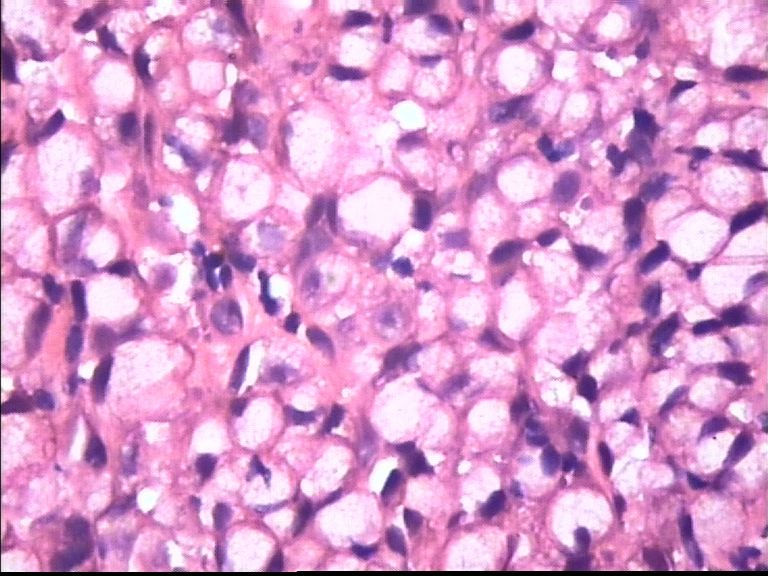

胃部溃疡3cm 53岁 男

仅此局部形态,应该是印戒细胞癌,最好有更多的背景资料

印戒细胞癌

倾向印戒细胞癌

诊断印戒细胞癌

印戒细胞癌高度可疑,建议做:CK、CD68、PAS帮助诊断。